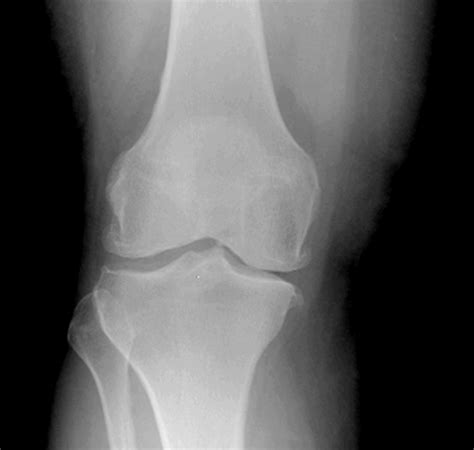

New Osteoarthritis Treatment Guidelines from the American College of ...